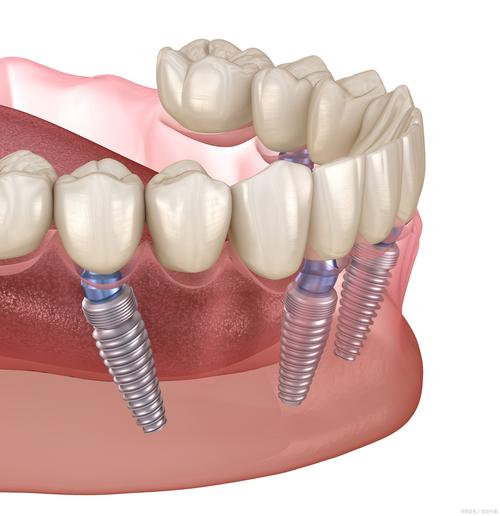

从技术原理看,allon4的核心在于通过4颗特殊角度的种植体实现对半口牙列的稳定支撑,图片中可清晰观察到种植体的植入策略:前牙区通常采用垂直植入,位于两颗中切牙之间的牙槽嵴,而后牙区则呈倾斜角度(约30-45度)植入,利用颧骨或颧牙槽嵴的骨皮质增强初期稳定性,这种设计在CT影像或术中示意图中尤为明显,倾斜种植体像“斜钉”一样穿透骨皮质,形成机械锁定,即使牙槽骨严重萎缩也能避免植骨,图片中对比传统种植的骨量需求,更能凸显其优势。

术前图片常展示患者缺牙后的口腔问题,如牙槽骨吸收导致的“瘪嘴”、咀嚼功能丧失等,而allon4术前设计图则会通过3D打印模型或数字化导板,规划种植体的精确位置、角度及深度,确保种植体能避开重要的解剖结构(如下颌神经管、上颌窦),这些设计图与术中的实时影像对比,能帮助患者理解数字化技术的精准性,减少对手术的恐惧。